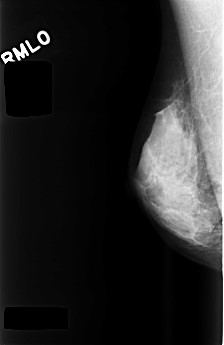

C_0477_1.RIGHT_MLO

C_0477_1.RIGHT_CC

RIGHT_CC LINES 4520 PIXELS_PER_LINE 2880 BITS_PER_PIXEL 12 RESOLUTION 50 NON_OVERLAY

RIGHT_MLO LINES 4480 PIXELS_PER_LINE 2912 BITS_PER_PIXEL 12 RESOLUTION 50 NON_OVERLAY